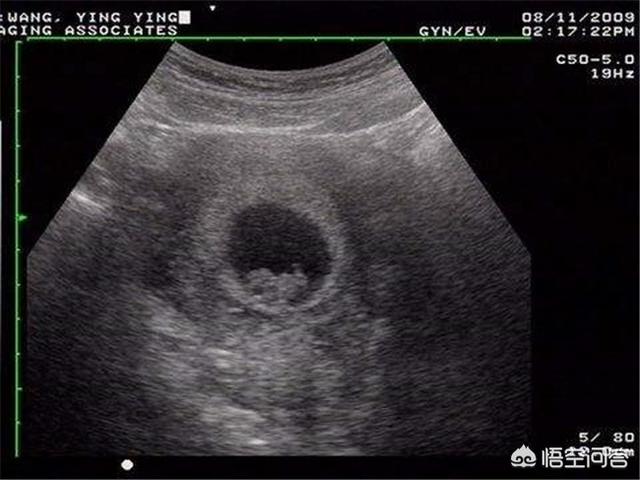

L'échographie B vérifie généralement le développement du fœtus et la position du placenta, et concerne rarement le problème des maladies fœtales. Seule l'échographie 4D permet de dépister les malformations fœtales. Votre question porte donc sur l'échographie 4D et non sur l'échographie B.

L'échographie 4D est une version améliorée de l'échographie b-scan, qui permet de détecter les malformations fœtales, les organes du visage et du corps du fœtus, les malformations des membres, telles que : fente labiale fœtale, syndactylie, quadruple cavité cardiaque, ectopie viscérale,...

Une échographie 4D pendant la grossesse permet de vérifier la présence de cardiopathies congénitales, d'hydrocéphalie, de fentes labiales et palatines, ainsi que le développement des membres du fœtus. L'échographie 4D permet également de voir l'image en mouvement du fœtus à l'intérieur du corps de la mère.

Communément appelé échographie 3D ou échographie 4D, il s'agit en fait d'un examen échographique visant à exclure la présence de maladies congénitales dans les différents systèmes et organes du fœtus.

L'échographie (échographie 4D) est un élément indispensable du test de grossesse. Elle est principalement chargée d'examiner la surface du corps du fœtus et divers organes pour y déceler des malformations. Par exemple : le cœur du fœtus, le cerveau, les reins et d'autres parties de la maladie.